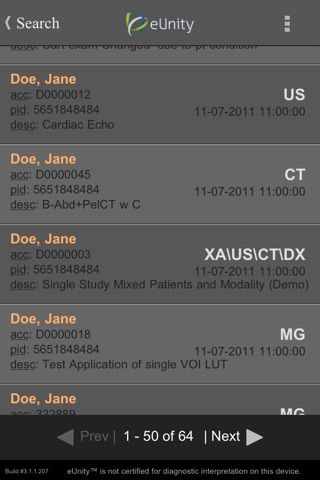

Simple, intuitive, secure - eUnity enables healthcare professionals to access, manipulate and collaborate over full quality medical images. View all image modalities, including X-ray, CT, MRI, color ultrasound and X-Ray angiography. Enhance your workflows by leveraging eUnity in grand rounds, consultations, referrals and reference. Connect to eUnity Server and extend the reach of your medical images to the point of care – wherever it may be.

• Query for your studies from the built-in search.